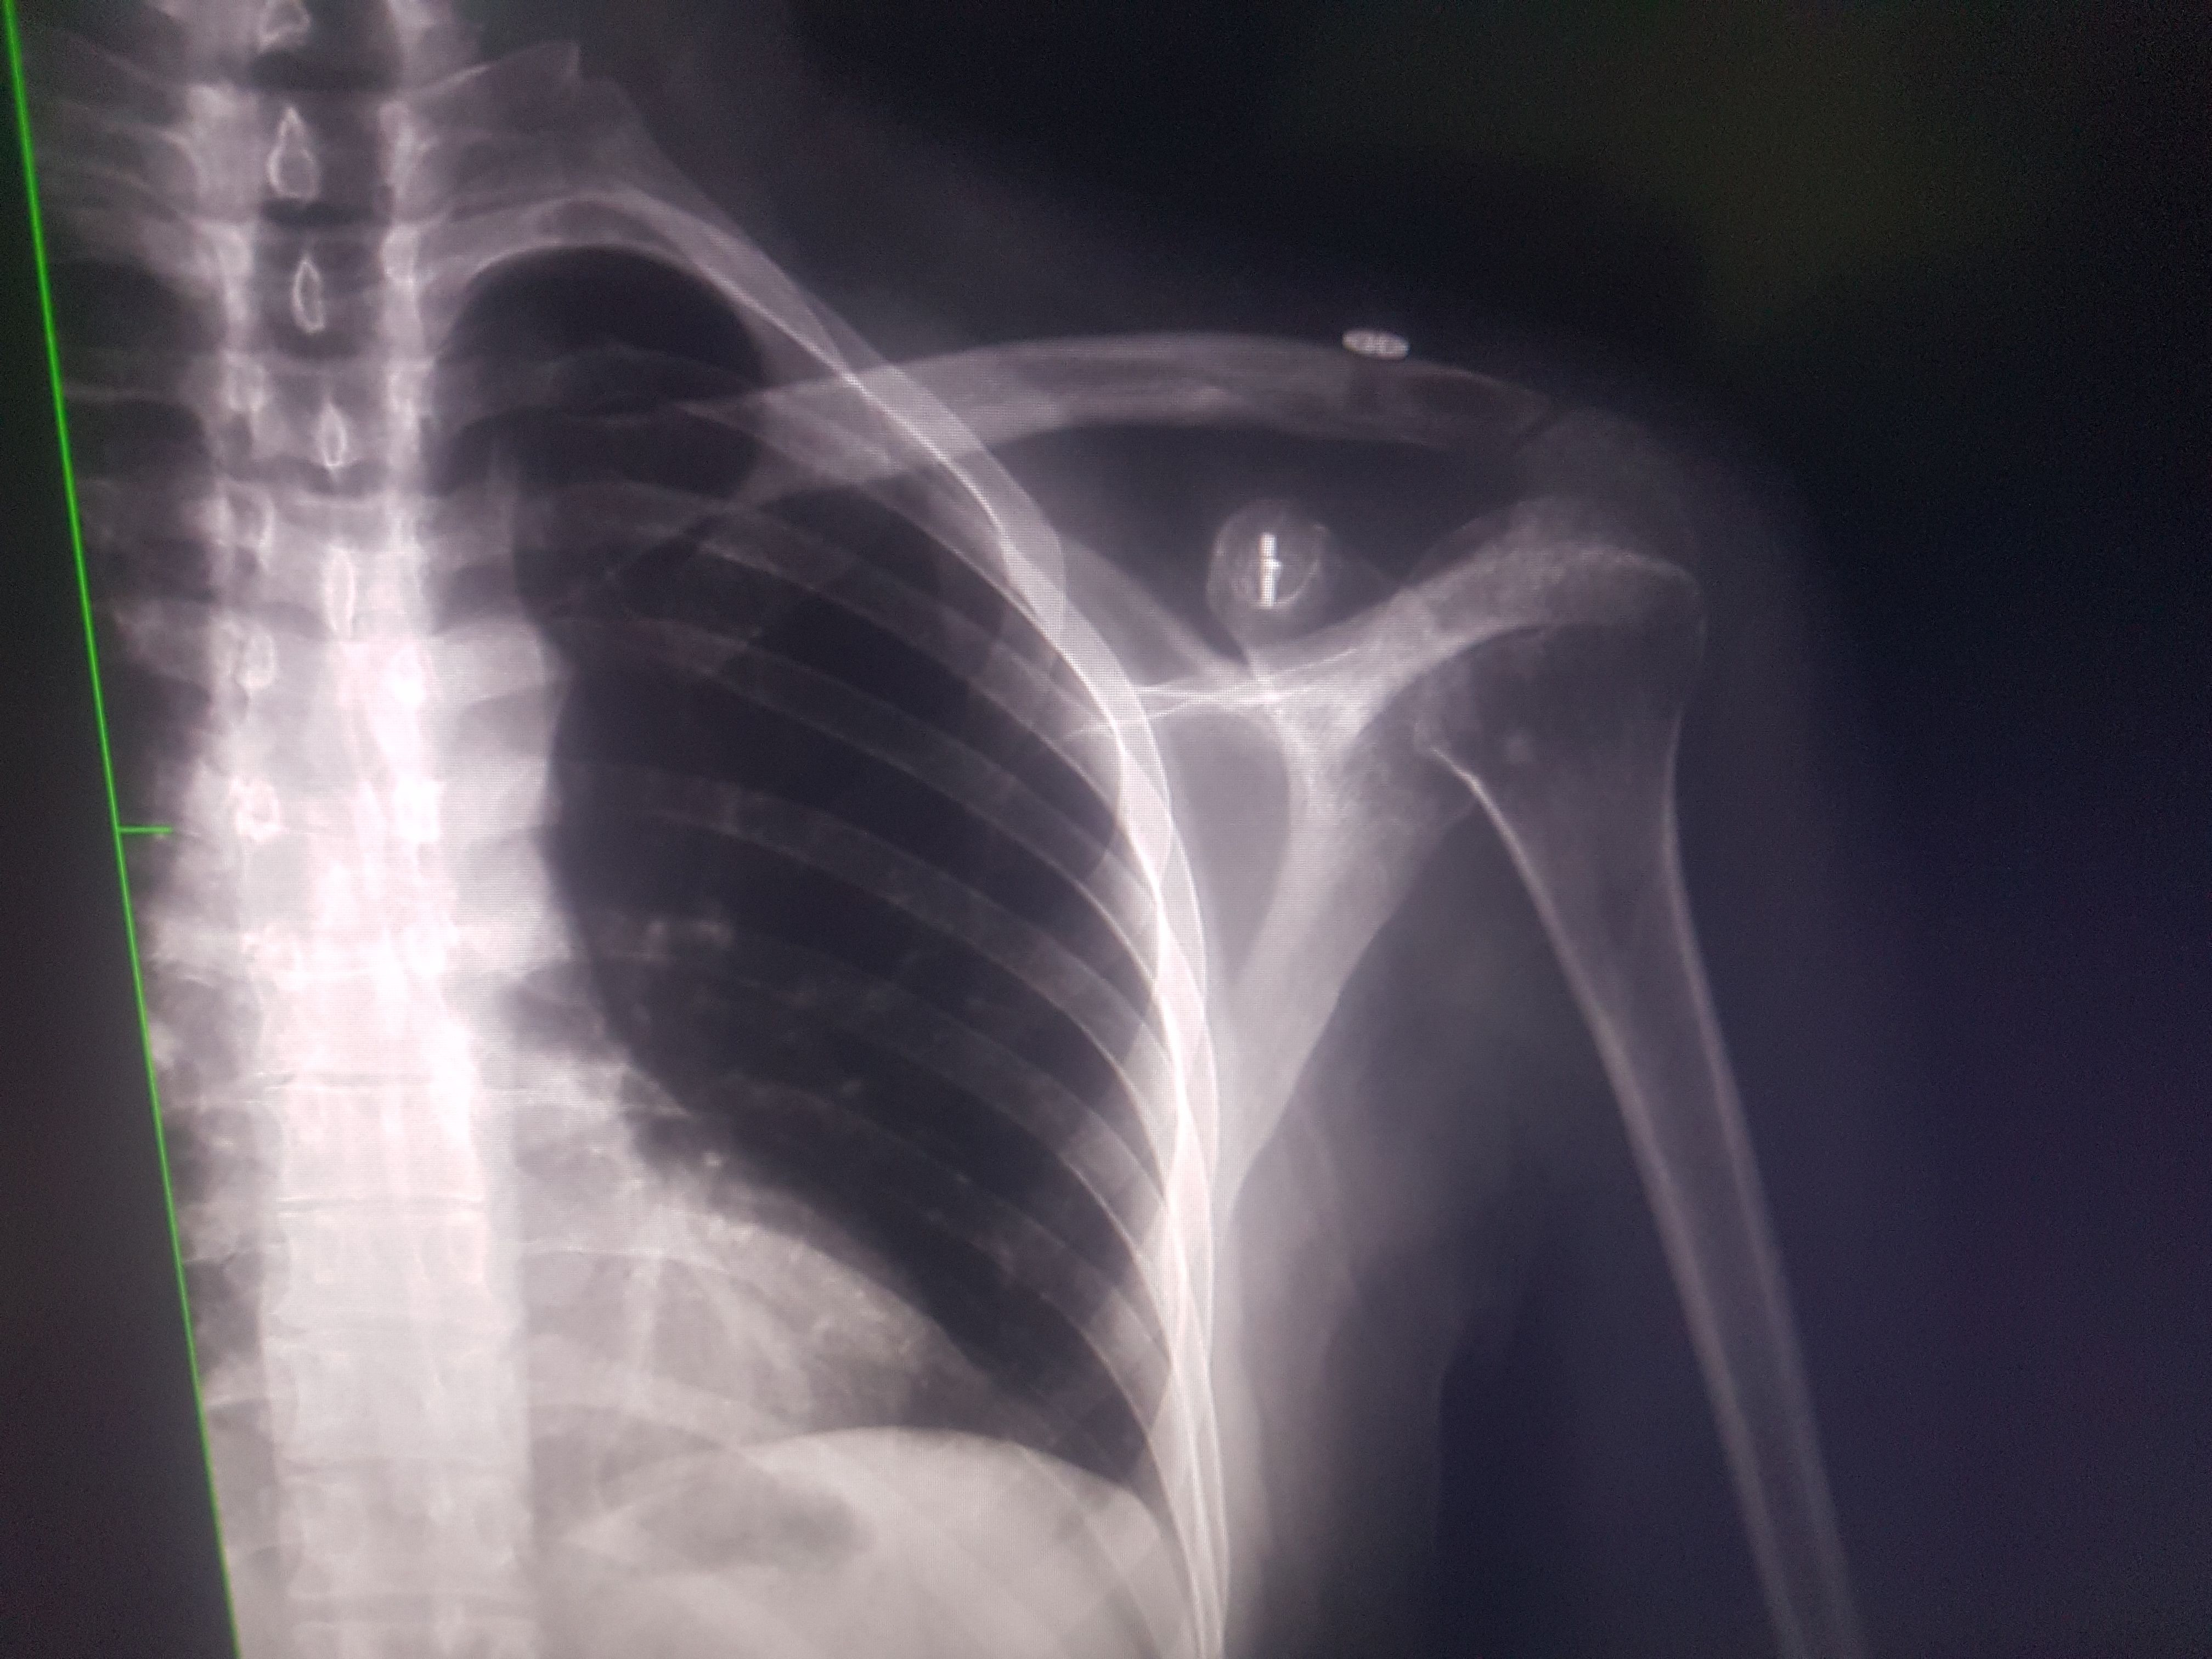

@caglar14 Aynı ameliyatı oldum 3. ay sonunda ip koptu. Çok sinirim bozuldu. Şimdi kemik yukarıda duruyor. Sadece benim mi başıma geliyor derken demek ki olabiliyormuş. Bir prof bana sağlam malzeme kullanmama kaynaklı demişti. Anlattığına göre ton kaldıran ip nasıl kopar mış ? Ya iyi tutturamadılar yada malzeme kötü dedi. Arada bir daha operasyon yaptırsam mı diyorum ama alıştım da. Siz bıraktınız mı öyle.